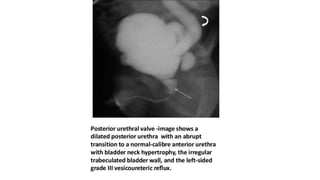

Posterior urethral Valve

โ€ข Congenital thick folds of mucous membrane located in the posterior

urethra (prostatic + membranous) distal to the verumontanum.

โ€ข Most common cause of severe obstructive uropathy in children.

โ€ข Almost exclusively in males.

โ€ข Leading cause of end stage renal disease in boys.

โ€ข Now rare for them to present with severe UTI and septicaemia -

diagnosis is generally made in early infancy and antenatal period.

โ€ข Procedure of choice for defining the valves.